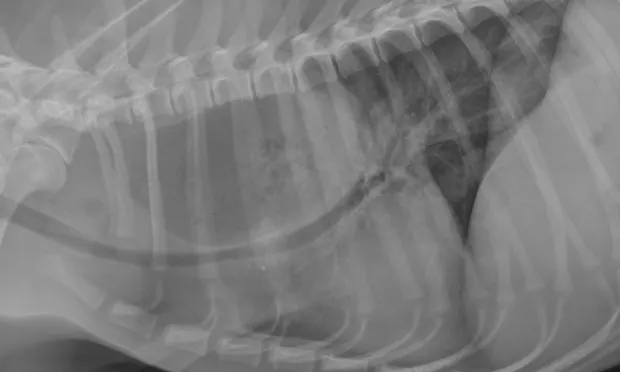

Diagnosing Megaesophagus

If a dog is regurgitating food, a veterinarian should be consulted immediately. Diagnosis typically involves a thorough physical exam, chest X-rays, and a barium swallow procedure. This procedure helps assess the size of the esophagus and track how long it takes for food to pass through.